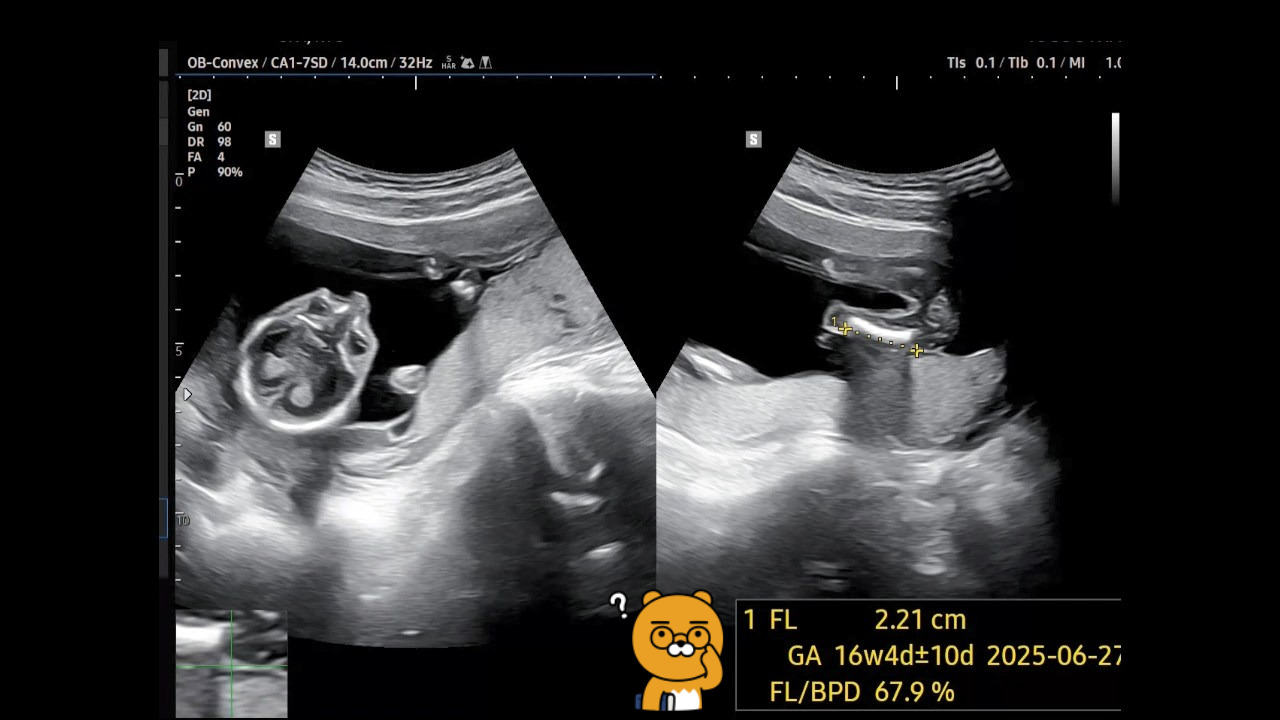

딸아이가 진찰을 받으면서 확인한 초음파 사진을 저에게 보내주었습니다.

초음파 사진은 4분이 넘는데 제가 알아볼 수 있는 항목만 캡처하여 보았습니다.

♬ GA(Gestational Age)는 임신 주수를 말하는 것인데, 임신 16주 4일±10일입니다. 지금이 임신 18주 차인데 왜 차이가 나는지 모르겠네요.

제 생각에는 장비마다 약간의 차이가 있는 것 같아서 이번에는 그냥 참고만 해야 할 것 같네요.

-> 딸애한테 나중에 들었는데 FL(Femur length, 허벅지뼈 길이)이 아직은 좀 덜 자랐다고 합니다. 뭐 웃으면서 숏다리라고 하네요.